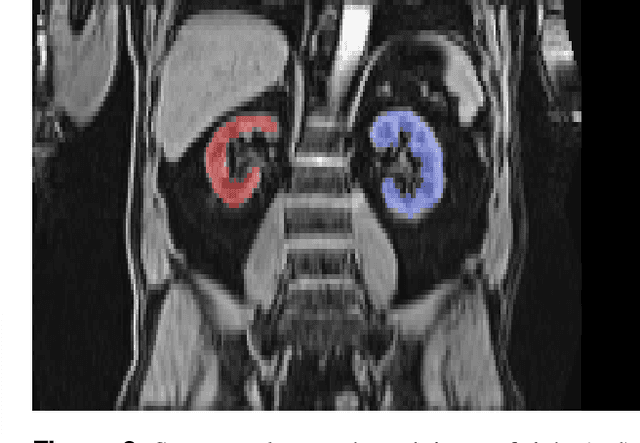

Abstract:The UK Biobank is collecting extensive data on health-related characteristics of over half a million volunteers. The biological samples of blood and urine can provide valuable insight on kidney function, with important links to cardiovascular and metabolic health. Further information on kidney anatomy could be obtained by medical imaging. In contrast to the brain, heart, liver, and pancreas, no dedicated Magnetic Resonance Imaging (MRI) is planned for the kidneys. An image-based assessment is nonetheless feasible in the neck-to-knee body MRI intended for abdominal body composition analysis, which also covers the kidneys. In this work, a pipeline for automated segmentation of parenchymal kidney volume in UK Biobank neck-to-knee body MRI is proposed. The underlying neural network reaches a relative error of 3.8%, with Dice score 0.956 in validation on 64 subjects, close to the 2.6% and Dice score 0.962 for repeated segmentation by one human operator. The released MRI of about 40,000 subjects can be processed within two days, yielding volume measurements of left and right kidney. Algorithmic quality ratings enabled the exclusion of outliers and potential failure cases. The resulting measurements can be studied and shared for large-scale investigation of associations and longitudinal changes in parenchymal kidney volume.